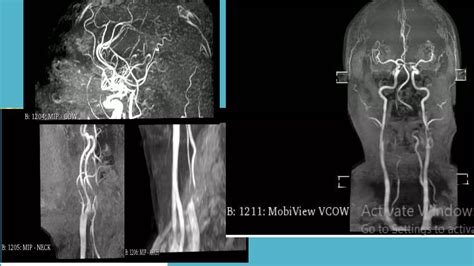

Magnetic Resonance Venography (MRV) is a sophisticated medical imaging technique that uses magnetic fields and radio waves to generate detailed images of the cerebral veins. Unlike a standard MRI, which primarily looks at the brain tissue itself, an MRV is specifically designed to assess blood flow and identify potential abnormalities within the venous system.

Doctors frequently use this scan to detect issues such as cerebral venous thrombosis (blood clots in the brain's veins), narrowing of the veins (stenosis), or other vascular anomalies that might be affecting cerebral circulation.

Magnetic Resonance Venography (MRV) Veins and venous blood flow Usually

Magnetic Resonance Angiography (MRA) Arteries and arterial blood flow Usually